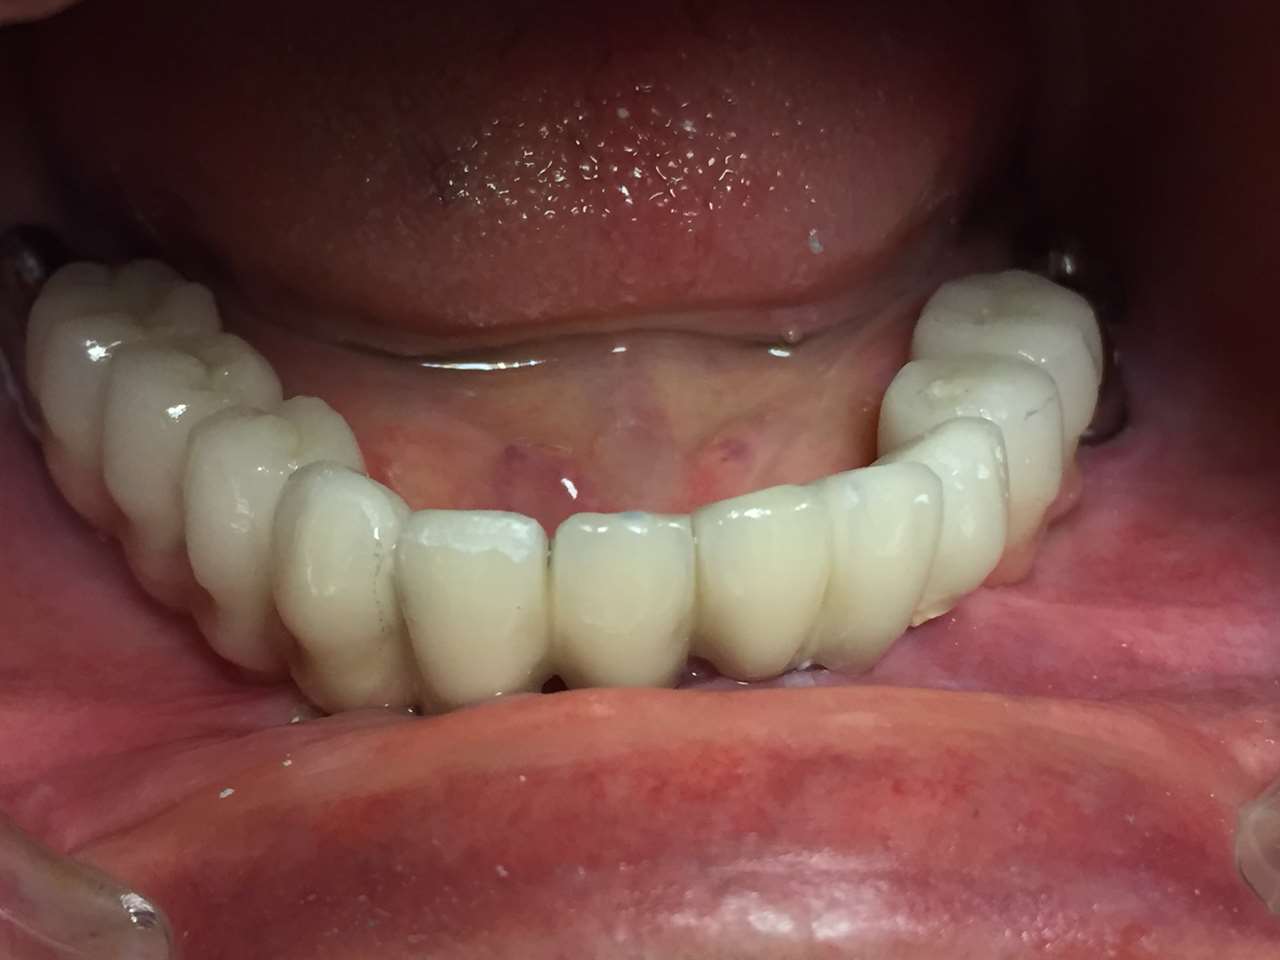

Elhanyagolt fogsor cseréje 2 nap alatt

2 nap alatt varázsoltuk ezt a szép esztétikus alsó, felső körhídat implantátumokkal megtámasztva a korábban elhanyagolt szájba. Az 1. nap 26 fogat távolítottunk el, mert annyira rossz állapotban voltak, és rögtön azonnal terhelhető IHDE svájci implantátumokat raktunk be, fentre 8, lentre 6 darabot. A sebeket összevarrtuk és intraorális szkennerrel digitális lenyomatot vettünk. 2 nap múlva pedig beragasztottuk a kész PMMA műanyag körhidakat. Dr. Kelemen Péter és a Symbion Fogtechnika munkája.